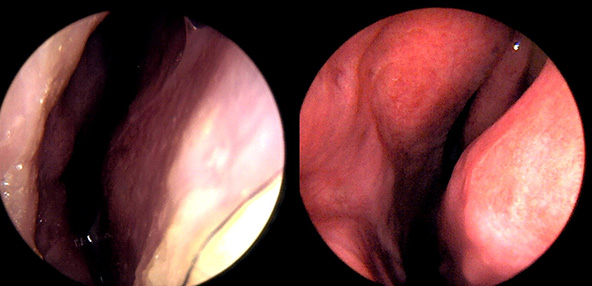

본 사진은 의료기관에서 진료를 본 환자이고, 전후 사진 인물이 동일인이며,동일조건에서 촬영이 되었습니다.